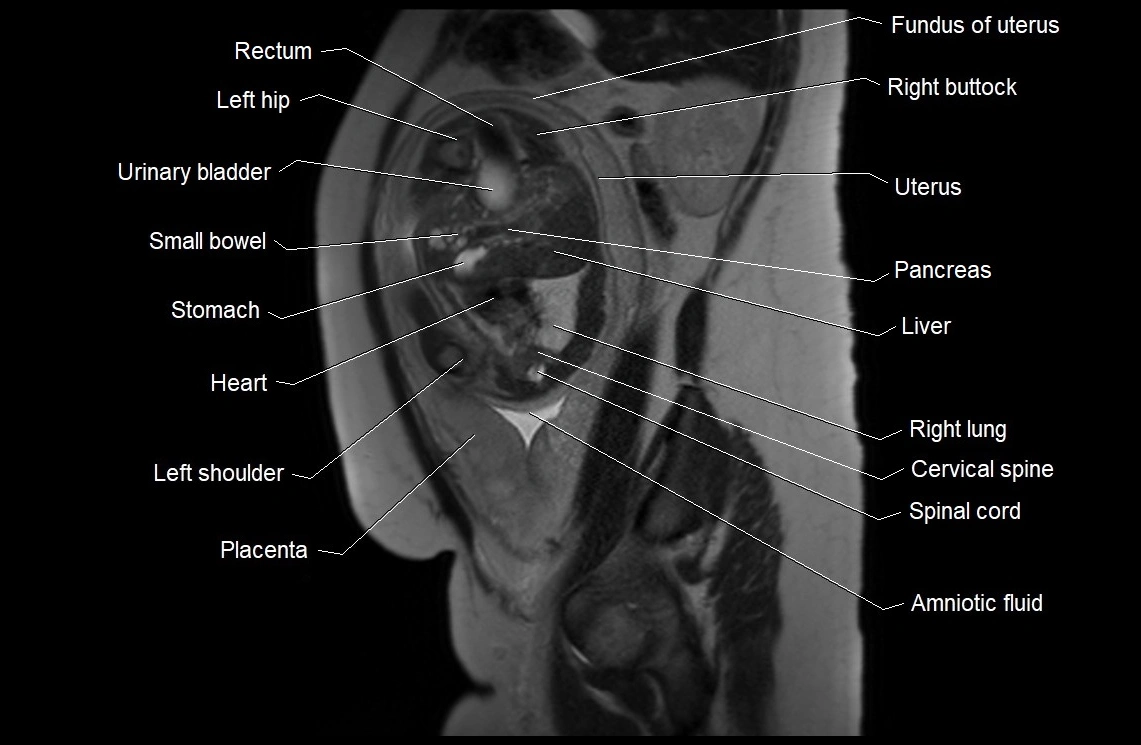

MRI Appearance

T2 HASTE (T2 GRE):

• Amniotic fluid shows very bright hyperintense signal

• Provides natural contrast against fetus and placenta

• Small particles (vernix) may appear as scattered hypointense foci within bright fluid

MRI image

image